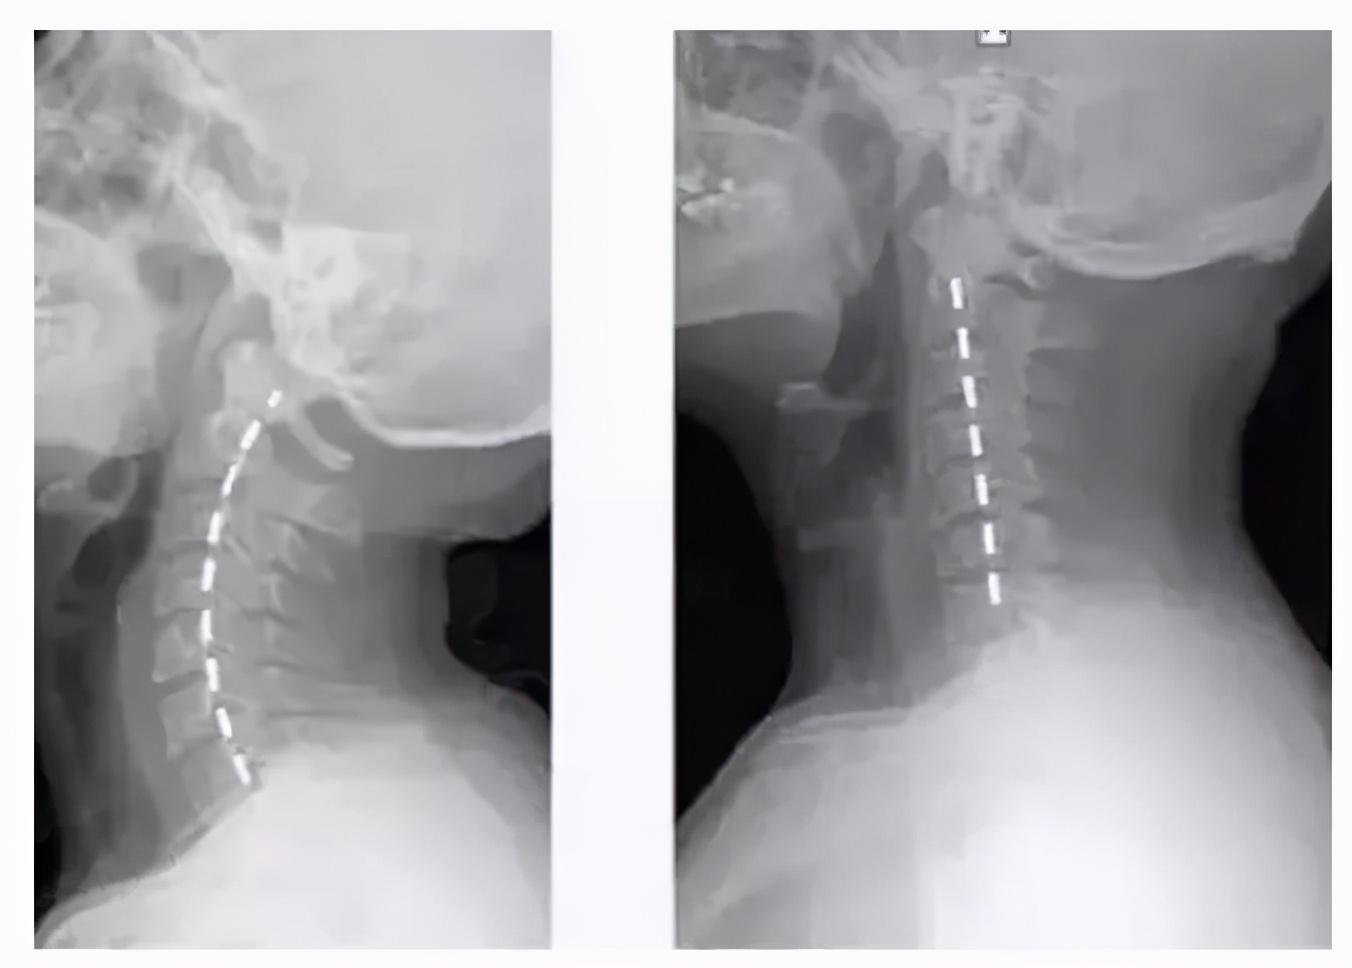

颈椎生理曲度变直,顾名思义,就是颈椎原本向前凸的生理弧度消失,变得平直甚至向后凸。正常情况下,颈椎应该有20-25°的向前凸曲度,这个曲度有助于分散头部重量,减轻颈部受力,保持身体平衡。然而,长期的不良姿势,尤其是长时间低头使用手机、电脑等电子设备,会导致颈椎曲度逐渐改变。